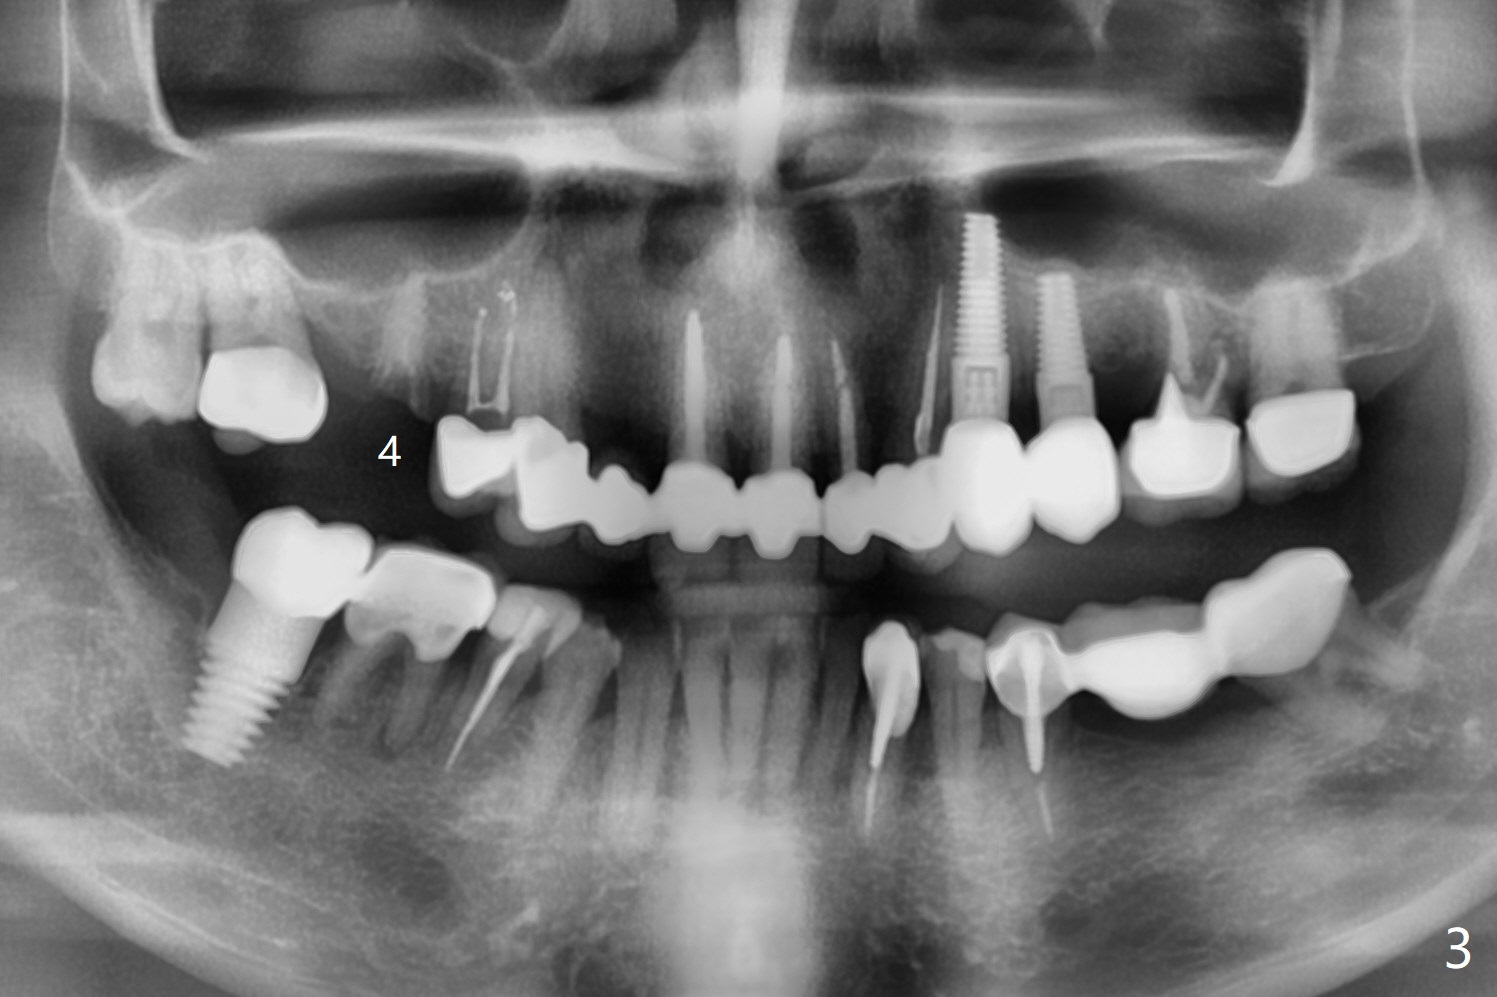

A 56-year-old man complains of food impaction under UR FPD (fixed partial denture, bridge). Floss goes through between #4 abutment and retainer (Fig.1 red arrow and *). After sectioning the FPD as indicated by black dashed line in Fig.2,3, try to initiate osteotomy at #3 with 1.2 and 1.5 mm drills for 5 mm (bone height) and 1.0 and 1.5 mm Tatum micro-osteotomes for sinus lift and place a 2x8.5 mm IS mini-implant. If it is feasible, place a 4x14 mm tissue-level implant slightly mesial at #4 (Fig.5). If not, place a larger one (5.0 mm) slightly distal for a cantilever FPD (Fig.4).